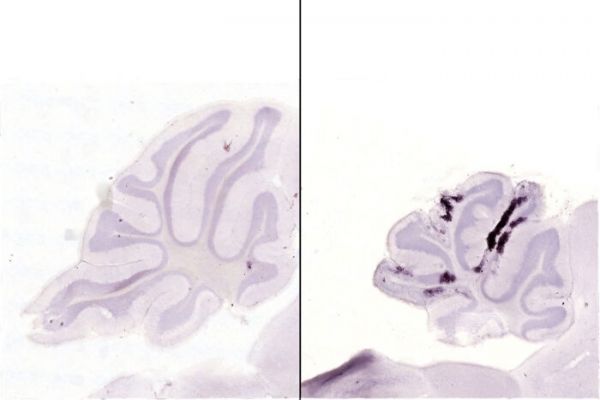

Image: Dark purple spots in the images of mouse brains indicate dying neurons. The brain of a mouse infected with a strain of Zika virus from Brazil (right) is shrunken and has more dying cells compared with that of a mouse infected with a strain from French Polynesia (left). Researchers at Washington University School of Medicine in St. Louis have found that the strain of Zika that circulated in Brazil during the microcephaly epidemic that began in 2015 was particularly damaging to the developing brain.  CREDIT: KEVIN NOGUCHI